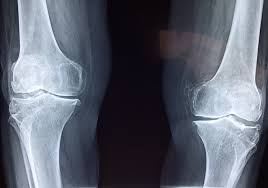

무릎 연골 손상 증상을 진단하기 위해서는 전문의의 상담과 검사가 필요합니다. X-ray나 MRI와 같은 진단 방법을 통해 손상의 범위와 정도를 확인할 수 있으며, 이는 적절한 치료 방법을 결정하는 데 중요한 역할을 합니다. 초기 진단이 이루어지지 않으면 무릎 연골 손상 증상이 악화되어 퇴행성 관절염으로 이어질 가능성이 높기 때문에, 무릎 통증이 지속되면 즉시 의료기관을 방문해야 합니다.